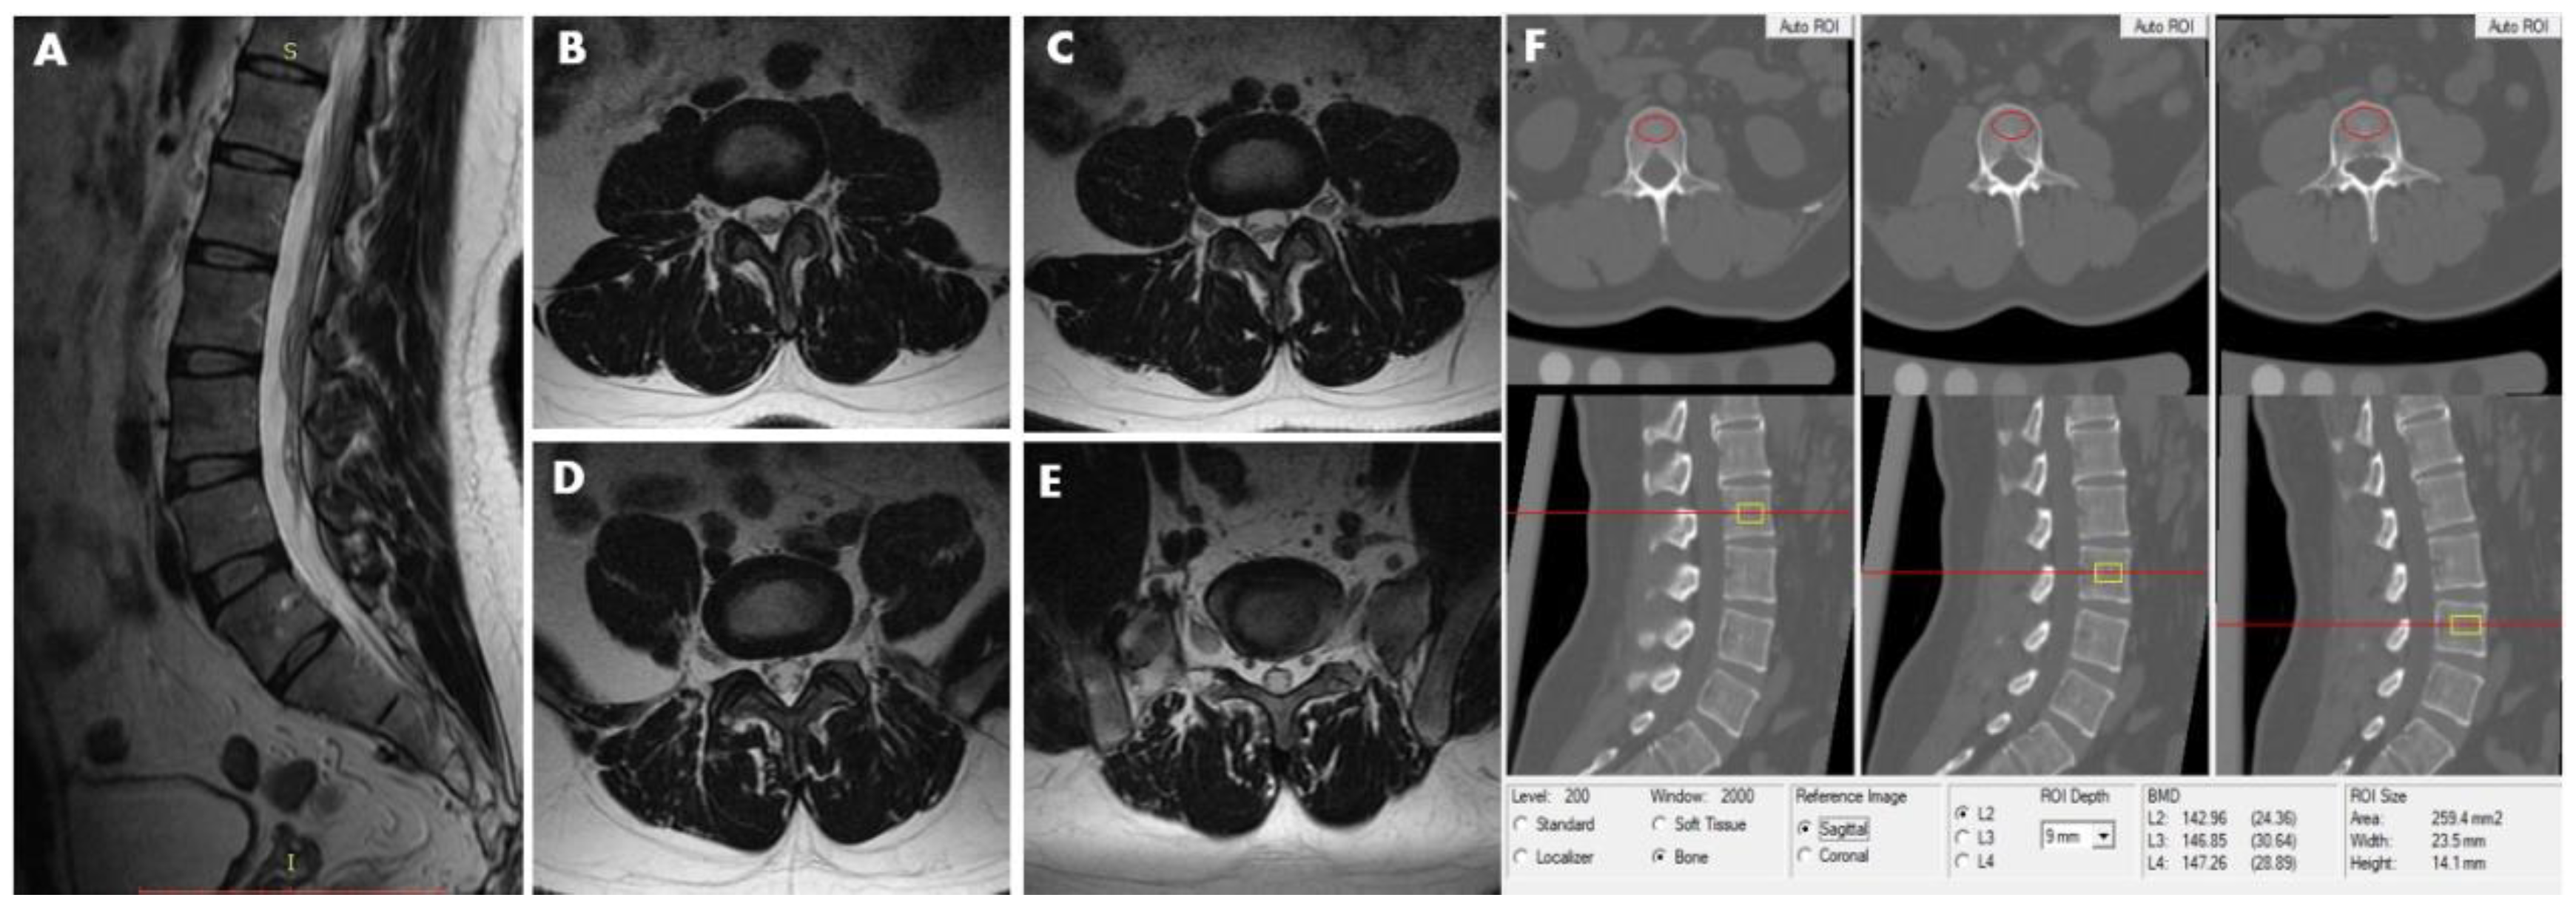

Figure 1.

This 40-year-old male participant was assigned to the non-LDH group. MRI (T2-weighted image) revealed no lumbar disc herniation from L2–3 to L5–S1disc. (A) Sagittal image. (B) L2/3 axial image. (C) L3/4 axial image. (D) L4/5 axial image. (E) L5/S1 axial image. (F) The measurements of L2, L3, and L4 vertebral trabecular volumetric bone mineral density (Trab.vBMD) are shown; the BMD of L2, L3, and L4 is 142.96 mg/cm3, 146.85 mg/cm3 and 147.26 mg/cm3, respectively. The average lumbar Trab.vBMD is 145.69 mg/cm3.